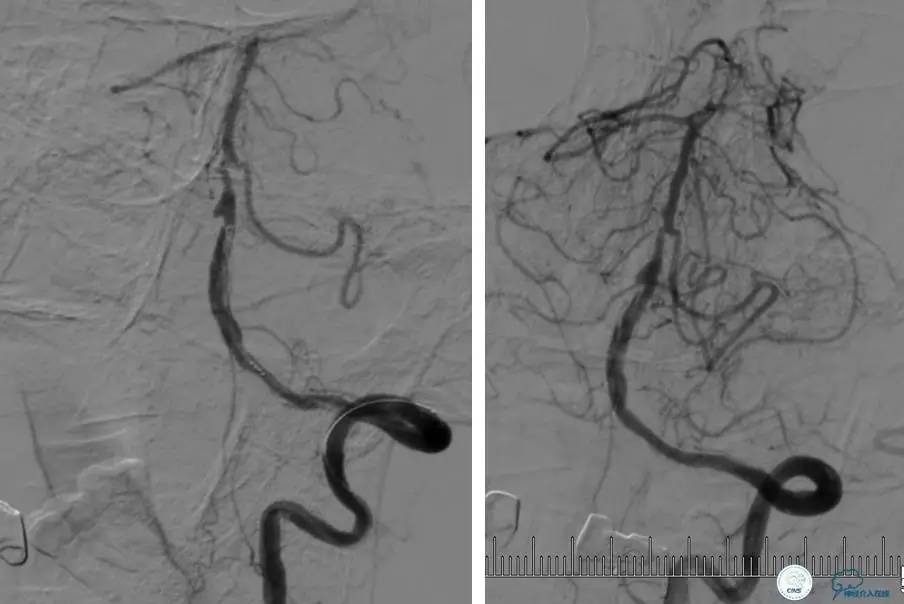

▼DSA示右侧椎动脉发育低下,弥漫性狭窄,可以看到左侧椎动脉反流,因此判断左侧椎动脉V4段CTO。

微导丝穿过闭塞段,微导管造影,球扩闭塞段,置入Wingspan支架,血流完全恢复正常。

患者术后2天再次出现卒中发作,药物治疗好转,此后病情稳定。半年后复查DSA,见支架闭塞,侧支循环开放。患者一般情况好,mRS:1分。